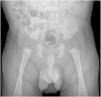

Varón de un mes de vida, asintomático (con ecografías prenatales normales) remitido a consulta de cirugía por identificarse en el control pediátrico una tumoración supratesticular derecha sugestiva de hernia inguinal. Dada la consistencia dura de la misma se realizó una ecografía que evidenció lesiones ecogénicas, heterogéneas y bilaterales con sombra acústica posterior (fig. 1) sugestivas de calcificaciones intraescrotales extratesticulares siendo la mayor supratesticular derecha de 1,2cm y radiografía simple de abdomen que identificaba múltiples lesiones calcificadas intraescrotales sin evidenciarse lesiones intraabdominales (fig. 2).